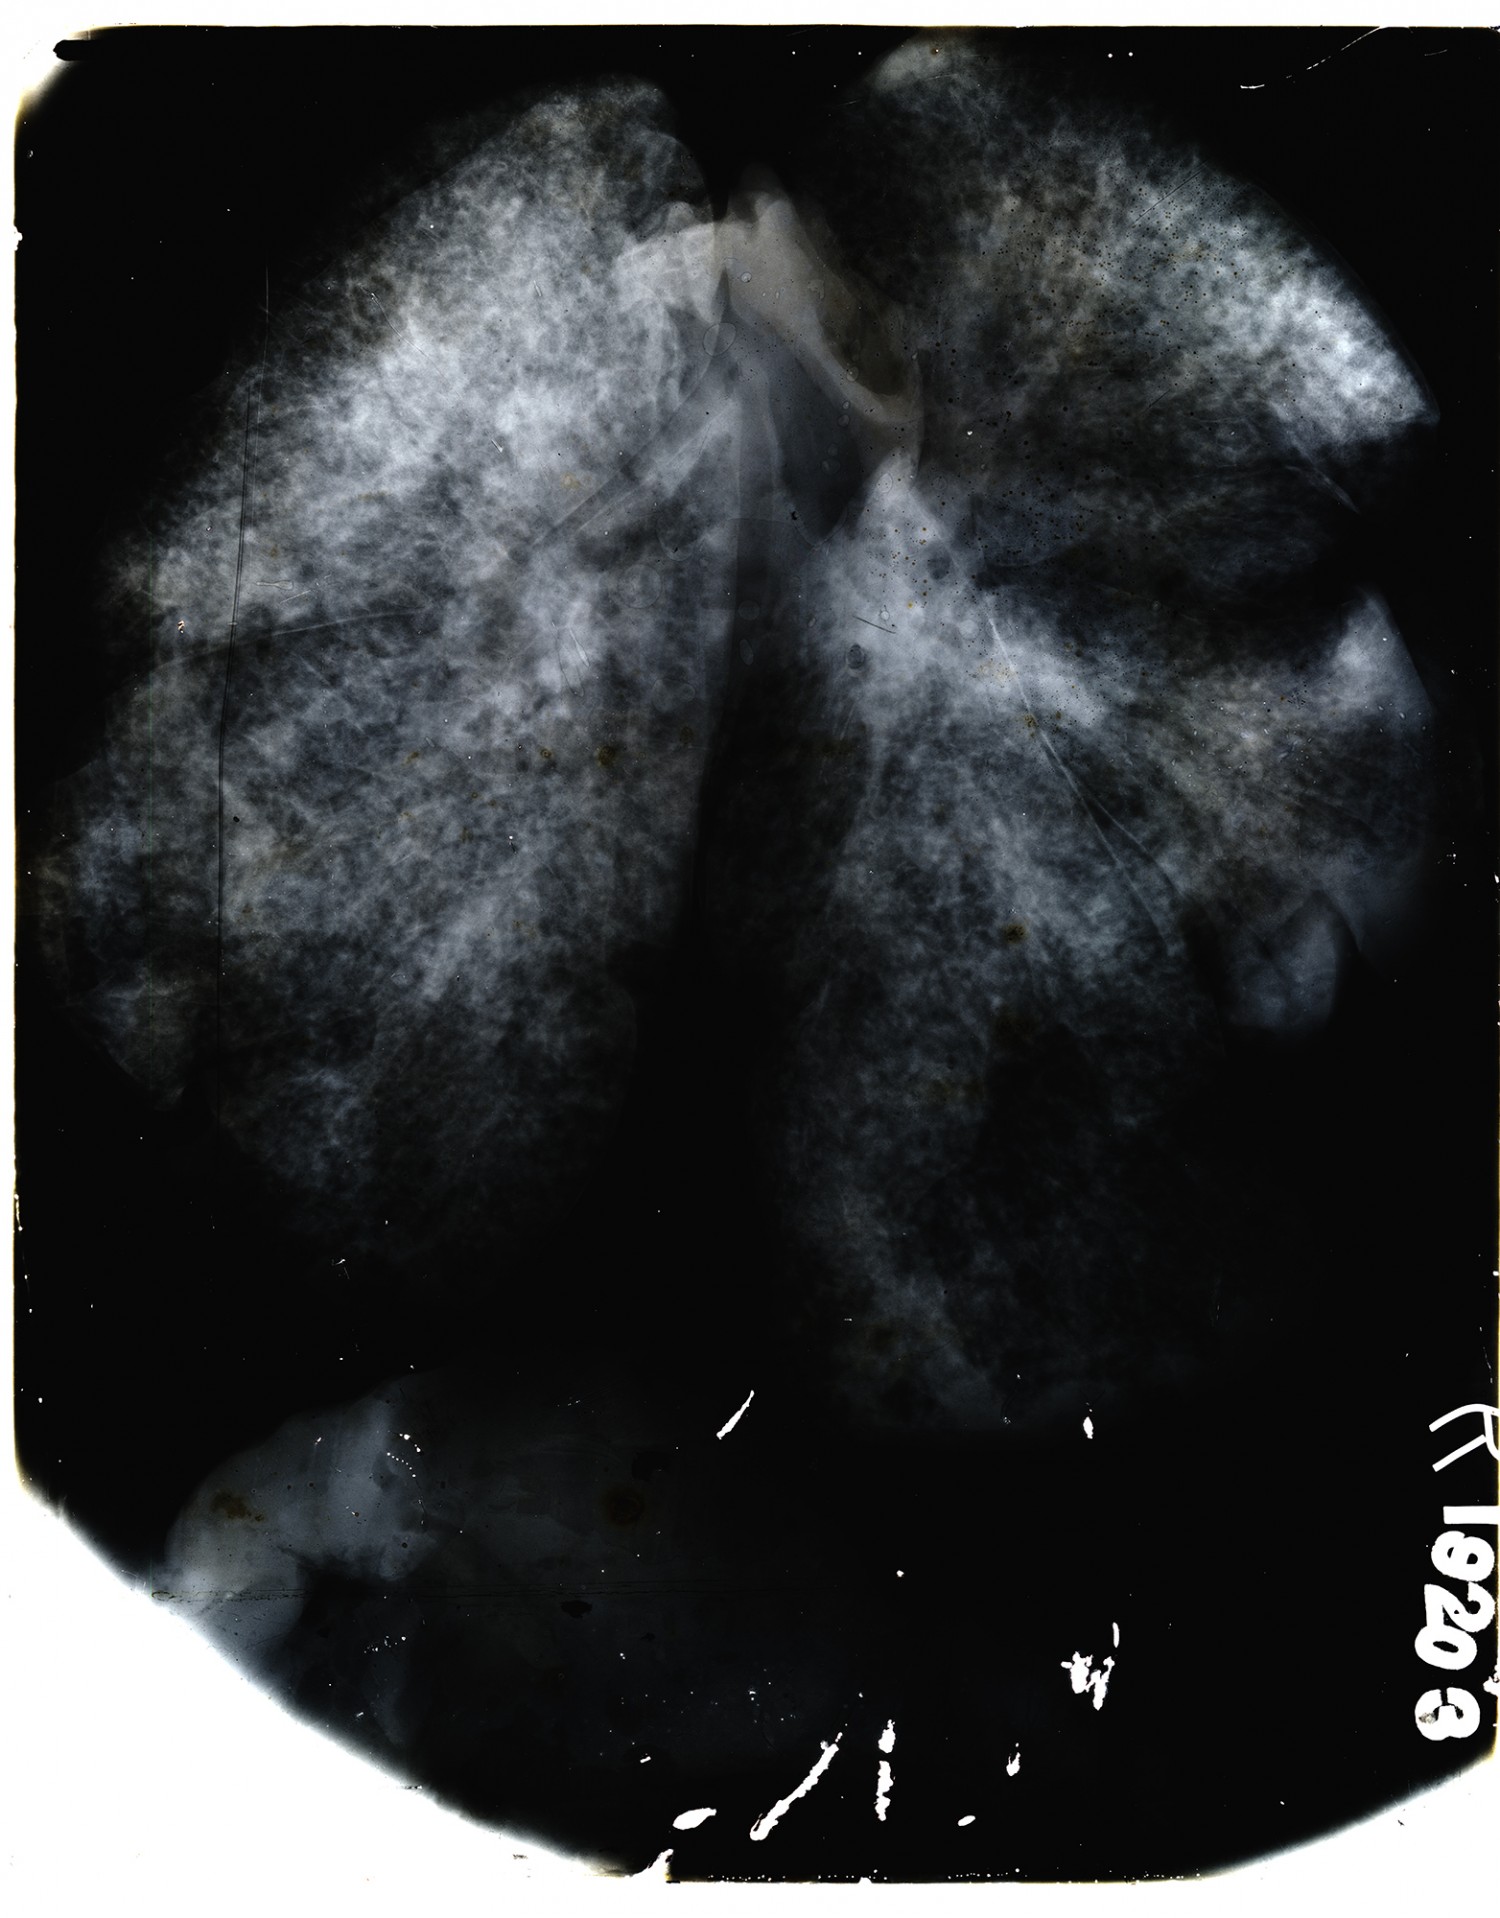

| Description | X-ray taken by Edwin C. Ernst of Base Hospital 21 in Rouen, France. Base hospital 21 was formed from faculty and students from Washington University School of Medicine. Ernst designed his own portable x-ray equipment to help quickly diagnose injured soldiers. |